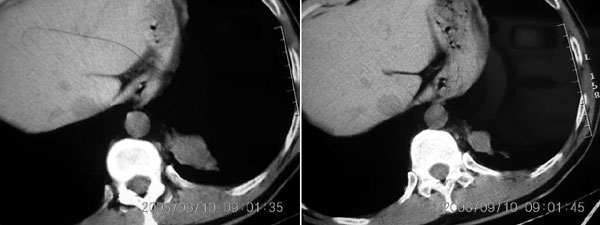

左下叶后基底段内胸主动脉旁可见一类梭形团块状影,边界较清楚,其内有小结节样高密度钙化影,肿块与胸主动脉可见条状影相连(见下图).

诊断:左下叶肺段隔离症.

病灶与膈肌相连 请增强确诊